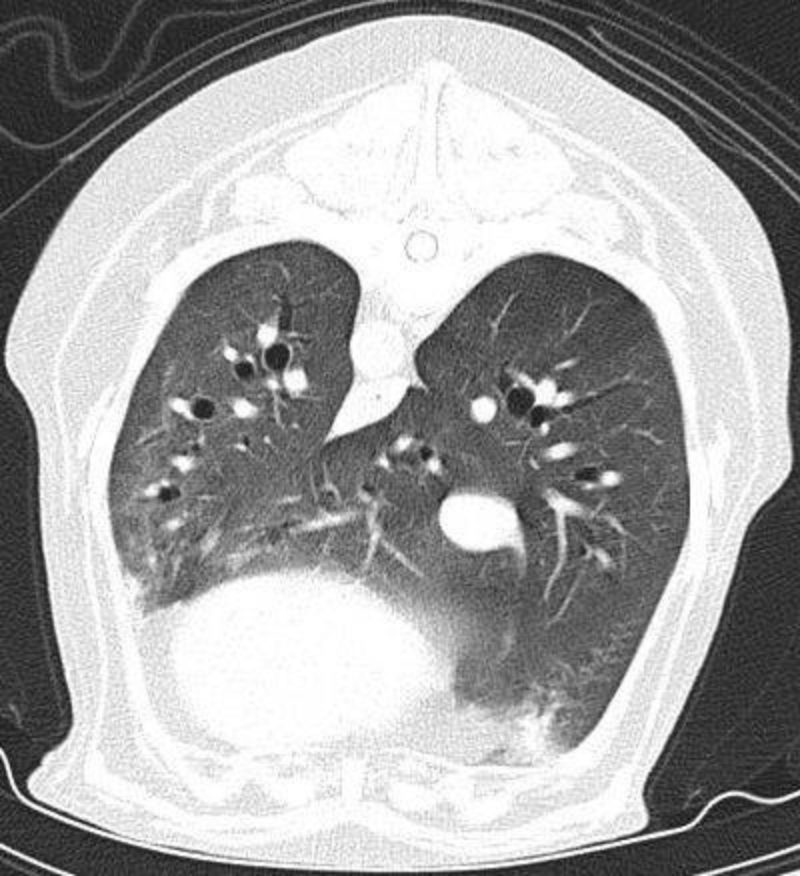

Tückischerweise sind Insulinome in den meisten Fällen sehr klein und sehr schwierig aufzufinden. Wir führten als nächstes eine systematische Suche nach dem Tumor durch. In der Regel sind insulin-ausschüttenden Geschwulste in der Bauchspeicheldrüse zu finden, jedoch können diese in seltenen Fällen auch in einer anderen Körperregion liegen. Zur Tumorsuche wird in der Tiermedizin standardmäßig zunächst ein Ultraschall des Bauchraums und Röntgenbilder des Brustkorbs in drei Ebenen durchgeführt. Ronjas Röntgenbilder der Lunge zeigten zum Glück keine Auffälligkeiten, jedoch konnte im dem Bereich der Bauchspeicheldrüse, der dem Zwölffingerdarm anliegt, eine verdächtige Stelle in der Ultraschalluntersuchung gefunden werden, die jedoch keine eindeutige Aussage zuließ.

Da Ronja trotz der Kortisontherapie immer wieder Episoden von Schwäche zeigte, galt es nun zügig zu einer Therapieentscheidung zu kommen. Die Computertomographie mit ihrer gegenüber dem Röntgen und Ultraschall deutlich verbesserten Darstellung von Gewebegrenzen ist hier die Methode der Wahl. Ein entscheidender Vorteil ist auch, dass mittels geeigneter Kontrastmittel die Darstellung und Abgrenzung von bösartigen Tumoren möglich ist. Insbesondere lässt sich mit der Computertomographie eine etwaige Streuung der Insulinome mit hoher Zuverlässigkeit abklären.

Tumor im Bereich der Bauchspeicheldrüse. Das Ergebnis der Computertomographie von Ronja zeigte tatsächlich im verdächtigen Bereich der Bauchspeicheldrüse einen Tumor, der nach einer Kontrastmittelgabe deutlich zu erkennen war. Weder in der Brusthöhle noch in der Bauchhöhle waren Metastasen nachzuweisen, was bedeutete, dass das Insulinom noch nicht gestreut hatte. In einem ausführlichen Gespräch wurden die Chancen und die Risiken einer Operation im Detail mit Ronjas Besitzerin besprochen. Bereits zwei Tage später konnte Ronja operiert werden. Bei der Operation wurde Ronja der Teil der Bauchspeicheldrüse entfernt, in dem sich der Tumor befand. Nach der erfolgreichen Operation war ihr Blutzucker innerhalb von kurzer Zeit im Normalbereich. Schon am nächsten Morgen empfing sie ihr Frauchen schwanzwedelnd, als diese zu Besuch kam und zeigte keinerlei Schwäche oder Kollabieren mehr. Bei den folgenden Kontrollen im Laufe des Tages war der Blutzucker weiterhin im Normalbereich, Ronja war beim Gassigehen überaus munter und wir entschieden uns, sie bereits am Abend nach Hause zu entlassen. Bereits in den nächsten Tagen konnte sie ihre alten Gewohnheiten wie zum Beispiel lange Spaziergänge wieder aufnehmen.